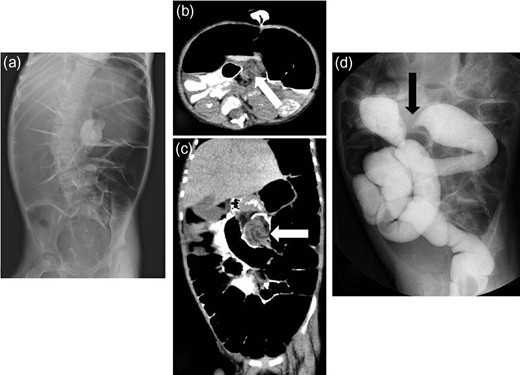

A 6-year-old girl presented with bilious vomiting and abdominal distension. She has Trisomy 18 and has undergone a tracheostomy and gastrostomy. Abdominal X-ray films showed dilatation of the bowel with gas (Fig. 1a). After injecting contrast medium through the gastostomy, retention of the contrast was noticed, which revealed intestinal obstruction. Based on plain computed tomography (CT) intestinal volvulus or intussusception was suspected (Fig. 1b and c). A barium enema revealed an incomplete obstruction or stricture (Fig. 1d). She underwent a laparotomy, and the intra-operative findings revealed a Meckel’s diverticulum, multiple intestinal tumors that were thought to be ectopic pancreas, and midgut volvulus associated with mesenterium ileocolicum commune and normal rotation of the intestine (Fig. 2a and b). Because of the massive content and gas in the bowel, a tube was inserted into the Meckel’s diverticulum to decompress the intestinal content. The midgut volvulus involved 180 degrees of counter-clockwise torsion, which was released with resection of the Meckel’s diverticulum and an appendectomy. Multiple intestinal tumors were resected, which were indeed diagnosed as ectopic pancreas. At one month post-operatively, she underwent adhesiolysis due to an ileus. She is currently doing well without torsion of the intestines.

Radiologic findings from Case 1. (a) Abdominal X-ray films showing dilatation of bowel with gas. (b and c) Plain computed tomography showing suspected intestinal volvulus or intussusception (white arrow: suspected lesion). (d) Barium enema revealing an incomplete obstruction or stricture (black arrow: suspected lesion).